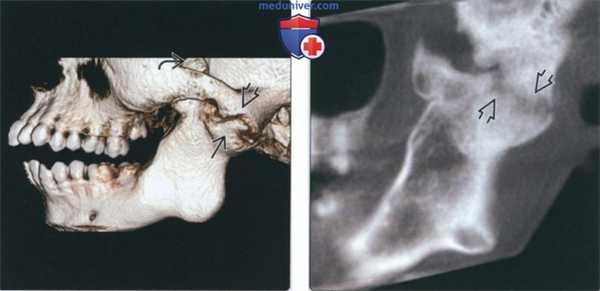

(Слева) На сагиттальной реформатированной КЛКТ определяется анкилоз левого мыщелка. Мыщелок склерозирован, суставное пространство отсутствует в зоне слияния. Височная кость неровная, склерозированная. Суставная ямка уплощена, суставное возвышение отсутствует.

(Справа) На панорамной рентгенограмме определяется костный анкилоз левого ВНЧС. Суставное пространство не визуализируется, форма мыщелка плохо различима. Венечный отросток удлинен, антегониальная вырезка углублена.